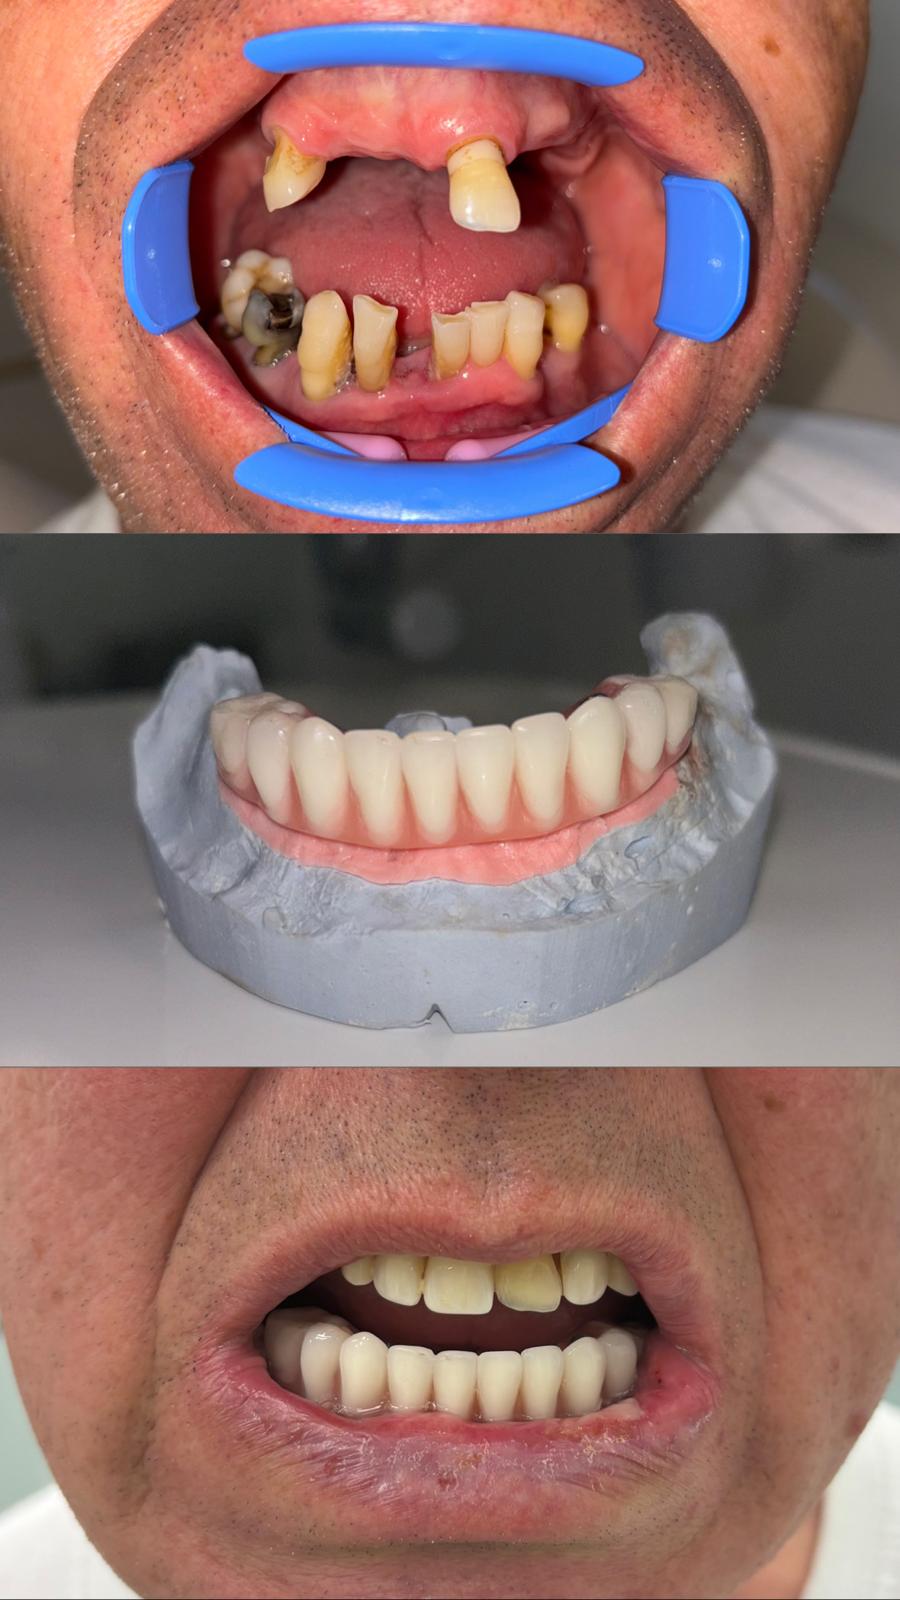

In Dental – Galleria

Rad1